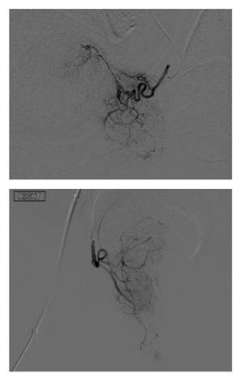

Prostate artery embolization, or PAE, is a non-surgical procedure that can improve lower urinary tract symptoms by blocking the blood flow to the prostate, thereby reducing the size of the prostate. It is performed by an Interventional Radiologist (IR), who is a specialist physician that uses X-rays and other imaging modalities to see in the body and treat diseases without surgery.

PAE is performed with local anesthesia and mild ‘twilight’ sedation and is generally an outpatient procedure, meaning the patient will go home after the procedure. Our IR physicians will insert a small catheter (which is a thin hollow tube) into the artery of the patient’s upper thigh or wrist, and with the use of X-rays guide the catheter to the arteries supplying the enlarged prostate. Tiny particles are then injected through the catheter into the prostate arteries, reducing the blood supply. This in turn shrinks the prostate gland, which alleviates the benign prostatic hyperplasia (BPH) symptoms.

PAE Figure 2